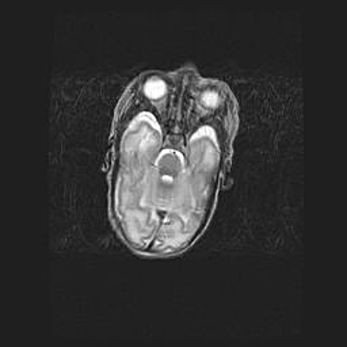

Подострая гематома правой гемисферы мозжечка.

Наружная гидроцефалия.

Возраст: 15 дней

Вес: 3100 г

Пол: женский

Окружность головы: 37 см

Срок гестации: 35-36 недель

При открытой наружной форме гидроцефалии у новорожденных расширяются и переполняются субарахноидные пространства.

Кровоизлияния в мозжечок имеют две клинико-анатомические формы: полушарные гематомы и кровоизлияния в червь.

К появлению этой патологии может привести: повреждения головного мозга, возникающие в результате асфиксии и гипоксии плода при беременности, или травмы во время родов. Редко гематома мозжечка может быть результатом первичной коагулопатии и сосудистой мальформации, диссеминированном внутрисосудистом свертывании, изоиммунной тромбоцитопении.